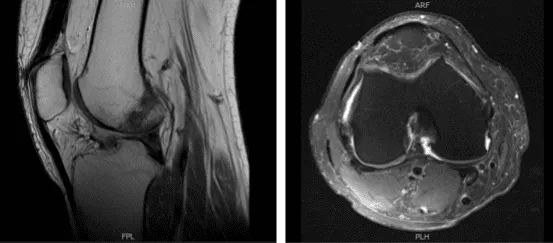

Resonancia magnética realizada y revisada por el médico. Se demostró que la rodilla izquierda del paciente está intacta en el menisco medial y lateral y no presenta lesión ósea aguda, pero sí un pequeño derrame articular. La troclea central presenta una fisura condral focal y fibrilación en la porción media del cóndilo femoral medial.

Sin embargo, la rodilla derecha del paciente previo, meniscectomía lateral parcial con diminuto cuerno anterior con una re-rotura en el cuerpo del menisco lateral. Debido a la extrusión del cuerpo, el menisco lateral causa osteoartritis tricompartmental demasiado leve a moderada con un derrame articular pequeño.